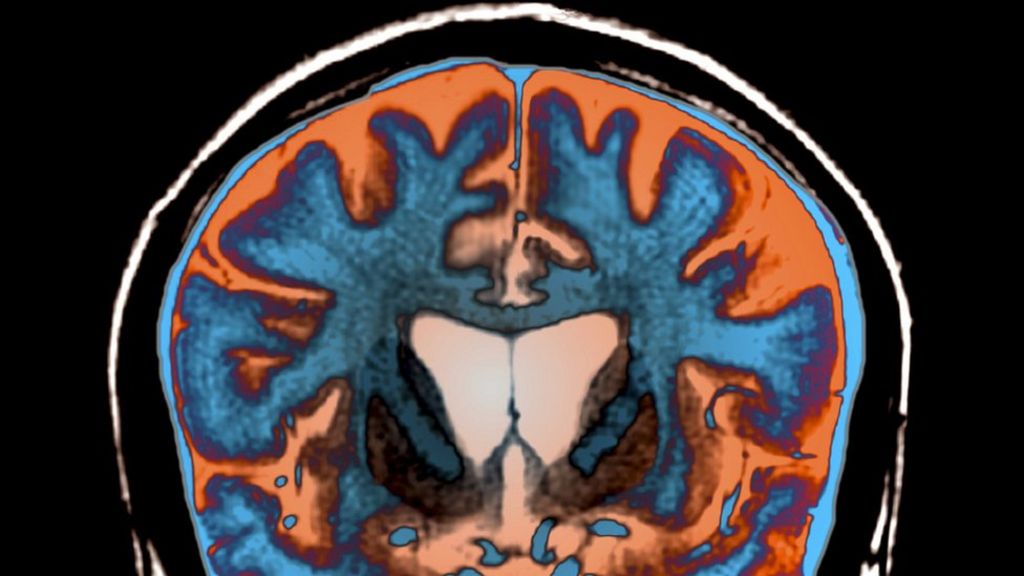

Measuring neurofilament light protein in blood predicts onset and progression of Huntington's disease in patients